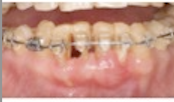

歯周基本治療の後に、矯正治療を開始し、挺出後下顎4前歯を抜歯21,22, 23.24.25歯に歯周組織再生療法EMDを行い、

治癒後、矯正治療、矯正後、垂直性骨欠損部15,23.24,25.37,45歯に再生療法。

22歯、抜菌. 27.36,16.46部にインプラントを埋入。

下顎4前歯の矯正的坻出

矯正による抜歯

矯正後の再生療法

上顎前歯の連結の判断